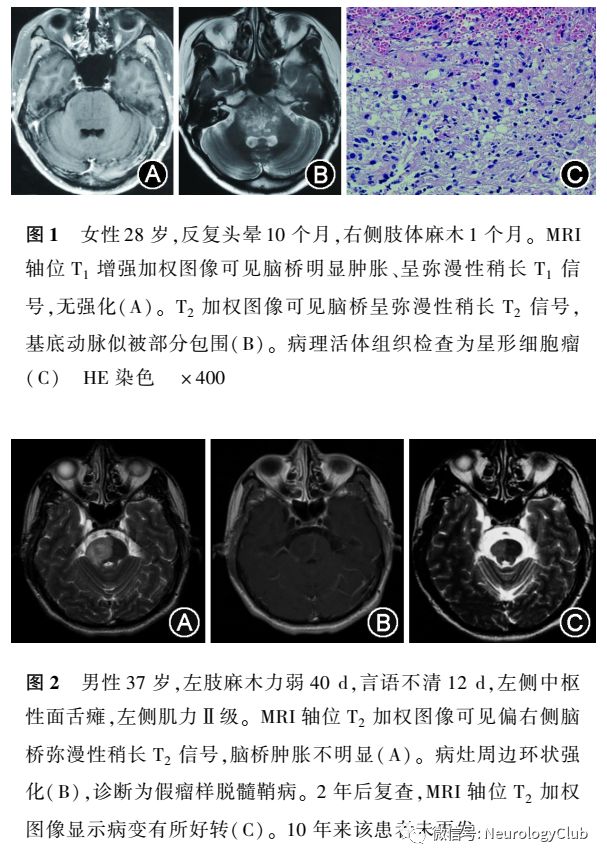

医师们习惯简单地用“胶质瘤”来代表脑内原发的神经上皮组织肿瘤,而实际上2007年已将神经上皮组织肿瘤分成星形细胞瘤、少突胶质细胞瘤、室管膜细胞瘤等9大类。星形细胞瘤又分成毛细胞型、弥漫性星形、胶质母细胞、大脑胶质瘤病等7种类型。临床医师也应适当懂得上述病理学分类的概念,以便对所要诊断的脑肿瘤进行分辨。不懂脑肿瘤病理,就很难全面理解肿瘤与非肿瘤性病变的特点与相应鉴别。如有的多中心生长星形细胞瘤类似血源性感染病灶,容易被误诊为多发感染病变(寄生虫)或多发转移瘤等。如果懂得脑肿瘤的生长特点、临床症候、影像特点等就不难做出相应的判断。如毛细胞型星形细胞瘤好发于儿童、青少年,以脑干中线结构及小脑为好发部位脑干虽然被肿瘤细胞所占满,但患者活动基本正常,只是稍有行走不稳、麻木或头晕等轻微症状(图1),这是由于肿瘤细胞在神经纤维中生长,并不破坏正常结构的原因但如果是脑干脱髓鞘病,哪怕仅仅是一小部分,患者临床症候也较明显(图2)。神经上皮组织肿瘤在CT上局部可呈稍高或高密度,而脱髓鞘病或脑炎往往都是低密度改变,因此,CT高密度有助于肿瘤与非肿瘤性病变的区分